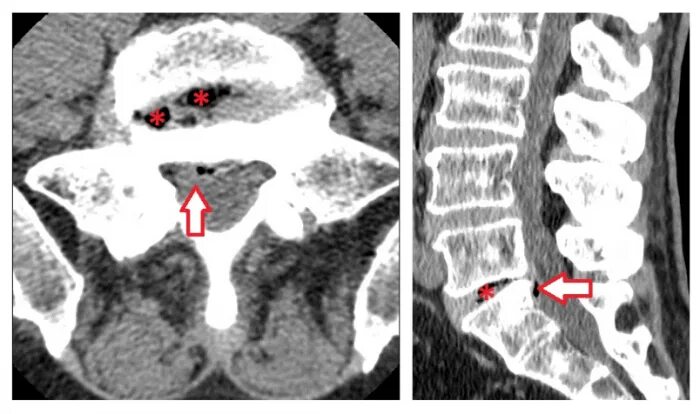

Грыжи на кт